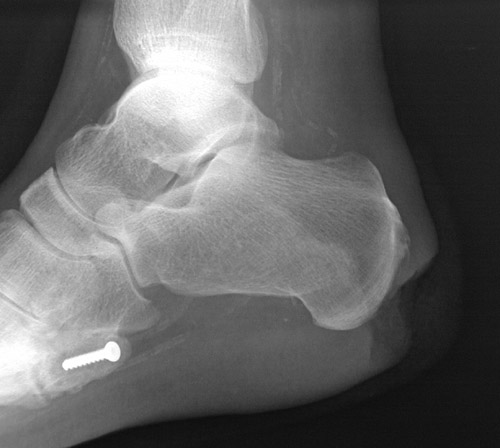

| This patient with diabetes mellitus developed an ulceration of the foot which was non-healing and became secondarily infected. The inflammation extended through the soft tissue and broke through the bone cortex into the underlying calcaneus, resulting in osteomyelitis marked by the area of lucency seen here. |